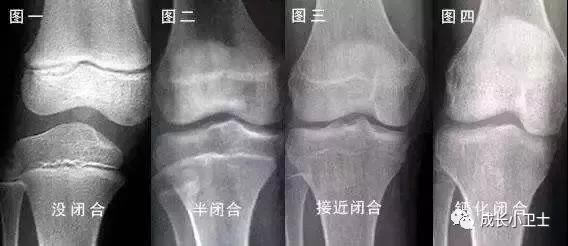

孩子到了醫(yī)院,進(jìn)行各項(xiàng)檢查可以幫助我們更進(jìn)一步的了解長(zhǎng)不高的原因。各項(xiàng)檢查包括血、尿檢查,肝、腎功能檢測(cè)和甲狀腺激素、生長(zhǎng)激素、生長(zhǎng)因子、腎上腺功能檢測(cè),這些檢查對(duì)于評(píng)價(jià)孩子的一般健康狀況和內(nèi)分泌腺體功能非常重要。女孩還要做染色體核型分析,因?yàn)橛幸环N染色體疾病叫做Turner綜合癥,特別鐘情于女孩子,不僅會(huì)影響身高,還會(huì)阻礙青春期的發(fā)育。同時(shí),需對(duì)左手掌、指進(jìn)行X光射線照片,以了解骨齡,判斷骨骺閉合的程度和生長(zhǎng)潛力。根據(jù)情況,有的孩子還需要進(jìn)行頭顱的MRI檢查,以排除先天發(fā)育異;蚰[瘤的可能性。

孩子年齡越小,骨骺軟骨層增生及分化越活躍,生長(zhǎng)的潛能和空間越大。一旦骨骺接近或已經(jīng)閉合,就耽誤了最佳治療時(shí)機(jī),任何方案均無法得到滿意效果。